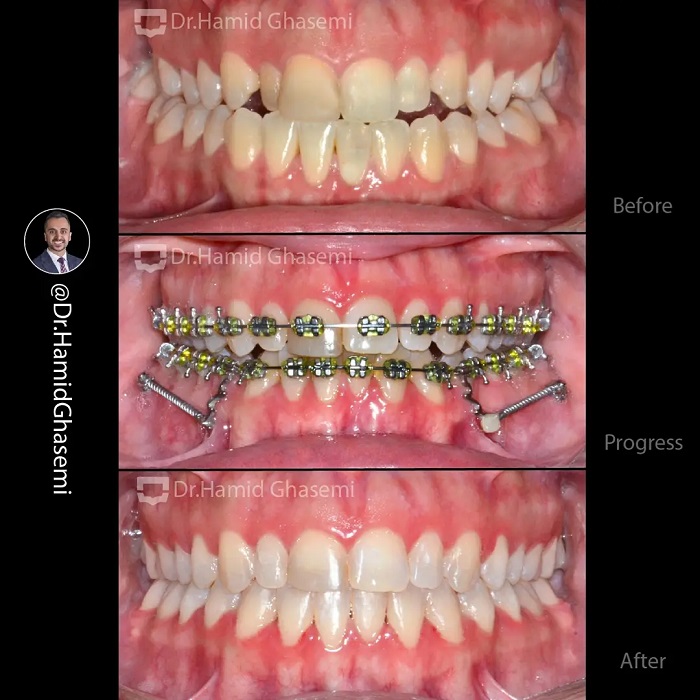

شماره پرونده : M.98_1549

درمان ارتودنسی بدون جراحی فک در کیس کلاس ۳ با بیرون زدگی فک پایین با استفاده از دیستالیزیشن فک پایین بعد از کشیدن دندانهای عقل فک پایین به کمک تکنیک Tads system ( اسکرو در باکال شلف فک پایین + فنرهای fatigue resistante ) در مدت ۲۰ ماه انجام شد. این کیس بوردر لاین نمونهای بارز از اهمیت انتخاب روش درمان ارتودنسی با و یا بدون جراحی فک را نشان میدهد که تا چه میزان امکان درمان ارتودنسی بدون جراحی فک با استفاده از تکنیک Tads system وجود دارد.

Non surgical orthodontic treatment of class 3 case with prognathic mandible done by distalizing lower dentition after extration of lower 3rd molars using Tads system (screws in buccal shelf + fatigue resistant closed coil spring) within 20 months. This case is an example of borderline case which the decision for surgical or non surgical treatment plan should be carefully planned to avoid surgery when ever it is possible with the aid of Tads system.